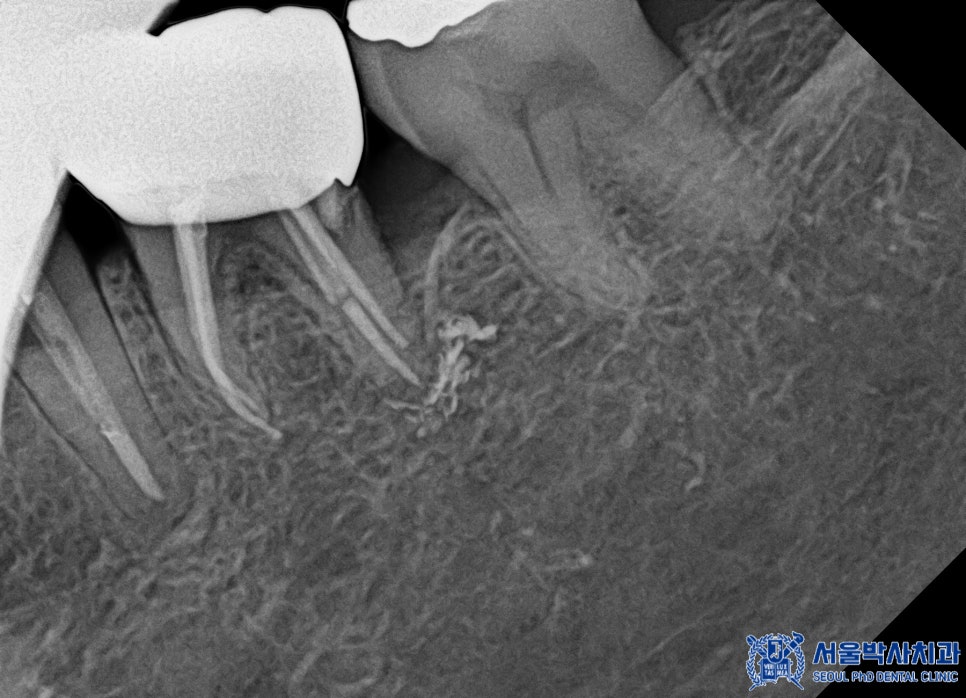

환자분도 MTA 신경치료를 통해

자연치아를 보존할 수 있도록

치료를 진행하였으며,

신경치료 마무리 후에는

크라운을 제작하였습니다.

서울박사치과는

자체 원내 기공소를 운영하고 있어,

크라운 제작 과정에서 보다 정밀하고

맞춤형 치료가 가능합니다.